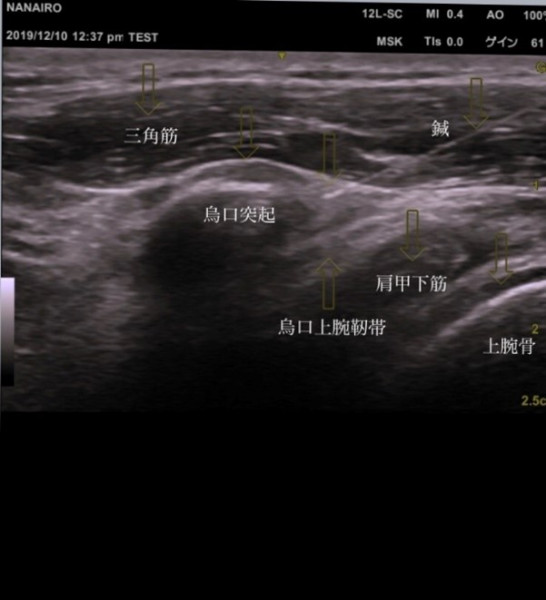

当院では、エコー検査を用いる事で、カラダの評価も大事にしております。

より安全に的確に悪くなっている原因部位に

はり治療が行えます。

エコーガイド下刺鍼